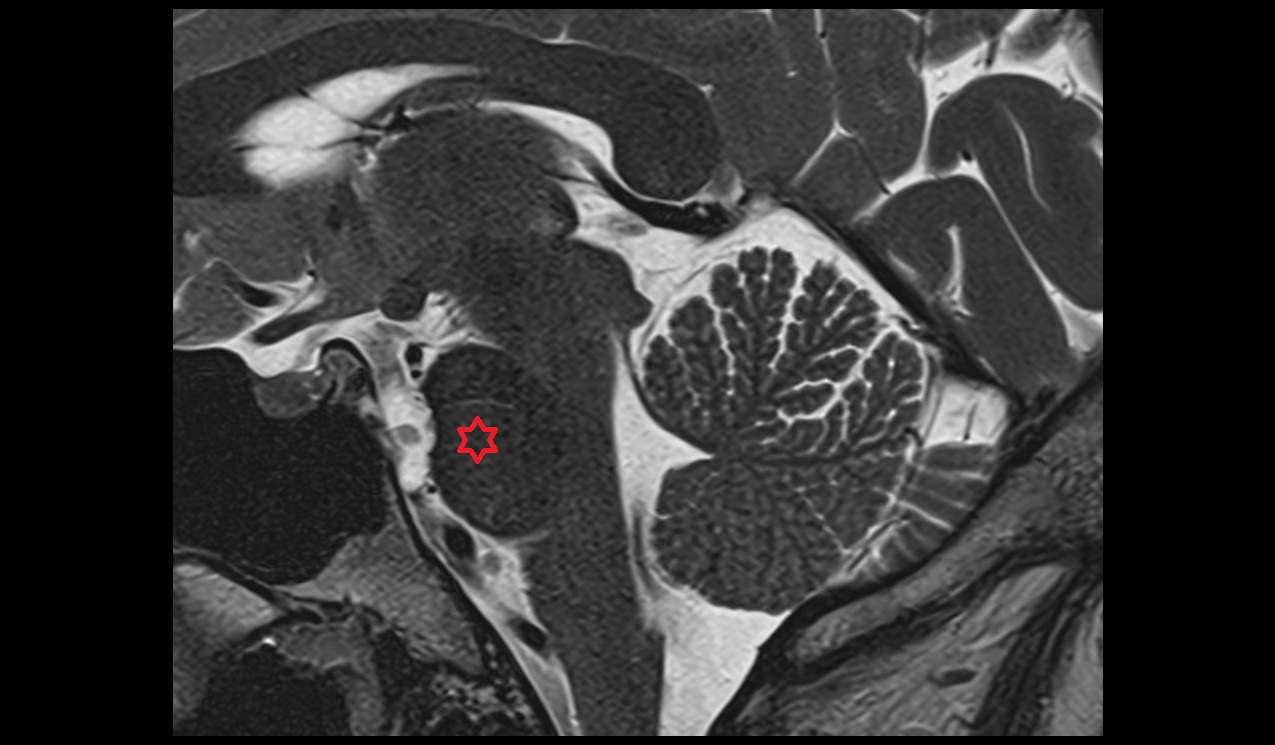

- Hippocampus